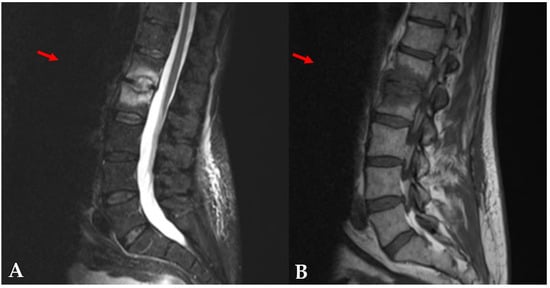

On 26 September 2018, a 59-year-old man was seen in consultation in our Infectious Disease Department for the follow-up of a left pneumococcal empyema and endocarditis caused by Streptococcus pneumoniae in June 2018, for which the patient was treated with amoxicillin for 6 weeks. His medical history included hypothyroidism, viral pericarditis in 1998, bacteremia due to Streptococcus gallolyticus in 2016, ulcerative esophagitis, and non-Hodgkin lymphoma (NHL). During the consultation, he reported suffering from lower back pain for 2 weeks. The lumbar pain was associated with paresthesia of the lower left limb. Magnetic Resonance Imaging (MRI) was performed a week later and showed edema associated with erosion of the L1–L2 vertebral endplates (Figure 1), suggestive of an intravertebral disc herniation or infectious spondylodiscitis. Secondary MRI was performed 10 days later and showed persistence of the previous images.

Figure 1. Magnetic Resonance Imaging of the patient. The sagittal STIR image (A) showed bright high-signal intensity of L1–L2 disc, which was well enhanced on the sagittal T1-weighted image (B).